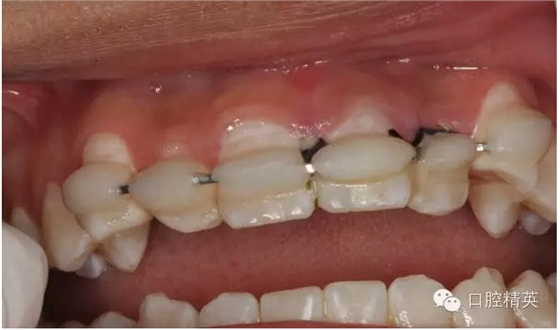

圖6.固定一個月后的唇側(cè)影像,牙齦及粘膜正常?;颊邿o任何自覺癥狀。

圖7.腭側(cè)口內(nèi)像,齦乳頭水腫消失

圖13.拋光完畢的牙面,齦乳頭色澤正常,無牙周袋。21不松動